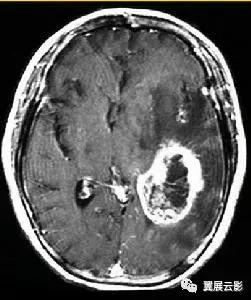

病例1:多发脑转移瘤

MR平扫转移瘤多呈等T1或长T1,等T2或长T2信号,瘤体内囊变坏死区呈明显长T1长T2信号,个别具有顺磁效应的转移瘤如黑色素瘤可出现短T1短T2信号,增强扫描病灶一般呈结节状或环状强化,转移瘤周围常有显著的脑水肿。多发脑转移瘤重点强调病变的位置发生在大脑,小脑,还是其他部位,病灶具体位于哪个脑叶,病灶是否位于皮,髓质交界区,病灶的形态和数目,平扫T1WI,T2WI信号特点及增强扫描所见,应密切视察瘤体内是否合并坏死,囊变等合并征象,本病需要与多发性脑脓肿,脑囊虫等疾病相鉴别,结合病史和原发肿瘤情况一般鉴别诊断不难。

病例2:单发脑转移瘤

单发脑转移瘤在报告书写时重点强调病灶的位置,形态,大小,平扫T1WI及T2WI信号特点及增强扫描时所见,重点要与胶质瘤,脑膜瘤和脑脓肿做鉴别。